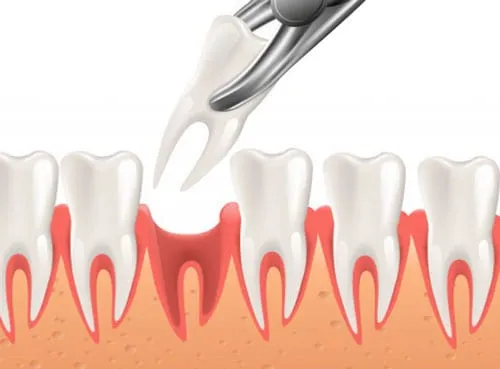

Baby tooth extraction is a dental procedure to remove a primary (baby) tooth that is decayed, damaged, or causing crowding in a child’s mouth. This procedure ensures proper oral health and allows permanent teeth to grow correctly.

Start from. Rp. 175.000

Permanent tooth extraction is a dental procedure to remove a damaged, decayed, or problematic adult tooth. This may be necessary when a tooth cannot be saved with fillings, crowns, or other treatments, or to make space for orthodontic treatment.

Start from. Rp. 400.000

Wisdom tooth extraction is a dental procedure to remove one or more third molars (wisdom teeth) that are impacted, crowded, or causing dental problems. Removing wisdom teeth can prevent pain, infection, and damage to adjacent teeth.

Start from. Rp. 1.000.000